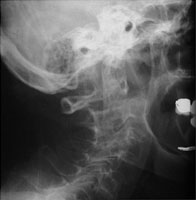

- Click on the image for a larger versionDLateral radiograph of the cervical spine. This demonstrates posterior translation of C1.